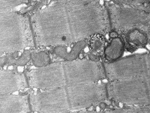

Autophagy is responsible for breaking down cell waste in order to prepare it for later removal or recycling. This cleaning process can affect any damaged cell component, such as mitochondria, crucial cell organelles responsible for providing cells with energy. The mechanism of autophagy specifically for mitochondria is called mitochondrial autophagy or mitophagy.

When the capacity “to clean up atypical mitochondria” is impaired, cells that remain in the body for a long time, such as neurons, heart cells and skeletal muscle cells, are especially affected. “The accumulation of damaged mitochondria over years leads to a deteriorated cell, thus increasing the risk of neurodegenerative diseases, such as Parkinson’s, cardiovascular diseases, some muscle dystrophies, and metabolic disorders such as diabetes and obesity”, explains Zorzano.

Although mitochondria were discovered more than 150 years ago, it was only a few years ago that these cell engines were linked to cell death programmes, otherwise known as apoptosis, mechanisms that control how long a cell lives. “These results may be relevant for cancer”, states Scorrano. “We know that decreased mitophagy cause an increase in apoptosis. So we could enhance cancer cell death by manipulating the mitochondria in these cells”.